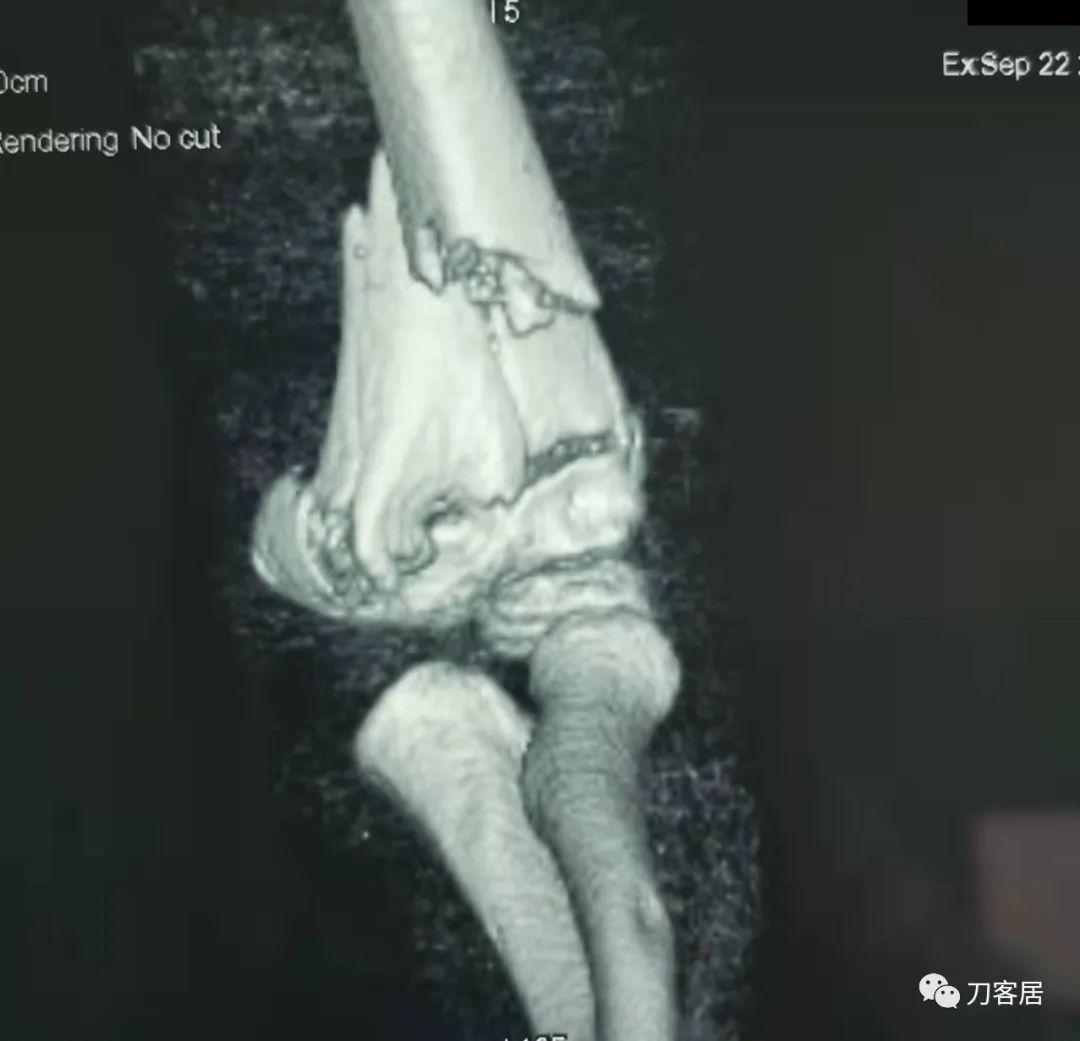

20210922当地省中医院三维CT01

20210922当地省中医院三维CT02

20210922当地省中医院三维CT03

20210922当地省中医院三维CT04

查体:左侧肘关节肿胀明显、疼痛、畸形,局部可见明显青紫瘀斑,左肘关节活动受限,肱骨远端环形压痛(+),局部可及异常活动及骨擦感形成,左上肢末梢桡动脉可触及,左侧腕关节及拇指背伸活动受限,左侧虎口区感觉麻木。辅助检查:自带X线及CT片示:左肱骨髁间粉碎性骨折。

入院诊断:1. 左肱骨髁间粉碎性骨折;2.左肱骨远端骨骺损伤;3. 左桡神经损伤。